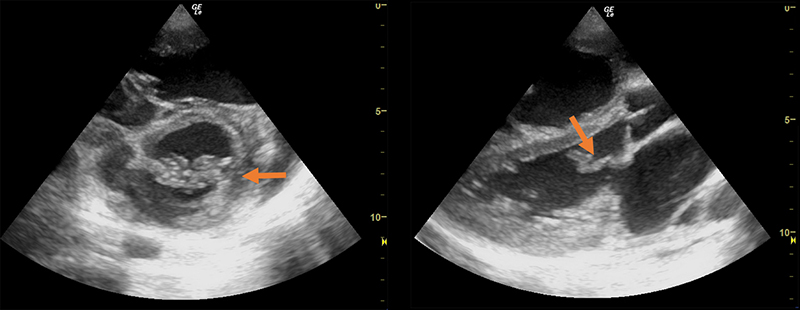

Figure 1. Parasternal short axis view (A) and long axis view (B) revealing thickened mitral valves (arrows). (Courtesy of Dr. Dan Kaminstein, Augusta University, Augusta GA, USA)

Figure 2. Apical 4 chamber view revealing mitral valve with abnormal hockey stick-like movement. (Courtesy of Dr. Dan Kaminstein, Augusta University, Augusta GA, USA.)

Figure 3. Parasternal long-axis view of abnormal hockey stick-like movement of thickened mitral valve.